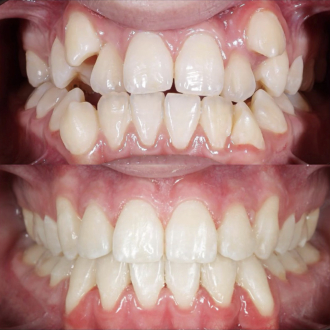

Клинический кейс комплексной реабилитации: проведена имплантация с последующим протезированием коронками, установлены коронки во фронтальном участке, виниры на нижние зубы и восстановлена ​​высота прикуса. В результате восстановлена ​​жевательная эффективность, стабилизированный прикус, равномерное распределение нагрузки и эстетическая улыбка.